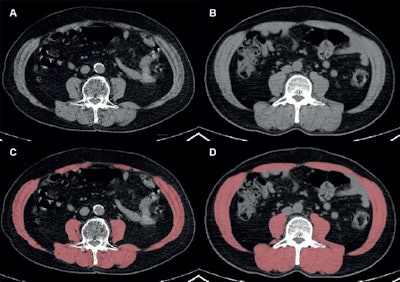

Automated segmentation of skeletal muscles at the level of the third lumbar vertebra in two representative patients with similar body mass index (BMI; calculated as weight in kilograms divided by height in meters squared) and different skeletal muscle statuses. (A, C) Axial noncontrast CT image (A) and red overlay image (C) at PET/CT in a 68-year-old male patient with a BMI of 28.1 show low skeletal muscle mass and myosteatosis, characterized by a skeletal muscle index of 44.2 cm2/m2 and a skeletal muscle radiodensity of 26.8 Houndsfield units (HU). (B, D) Axial noncontrast CT image (B) and red overlay image (D) at PET/CT in a 69-year-old male patient with a BMI of 28.4 show normal skeletal muscle mass and radiodensity, as indicated by a skeletal muscle index of 62.4 cm2M/sup>/m2 and a skeletal muscle radiodensity of 41.6 HU. Images and caption courtesy of the RSNA.